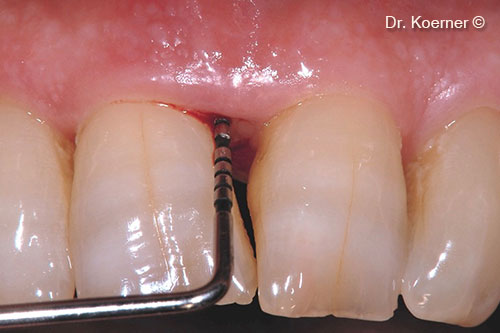

Pocket probing 9mm